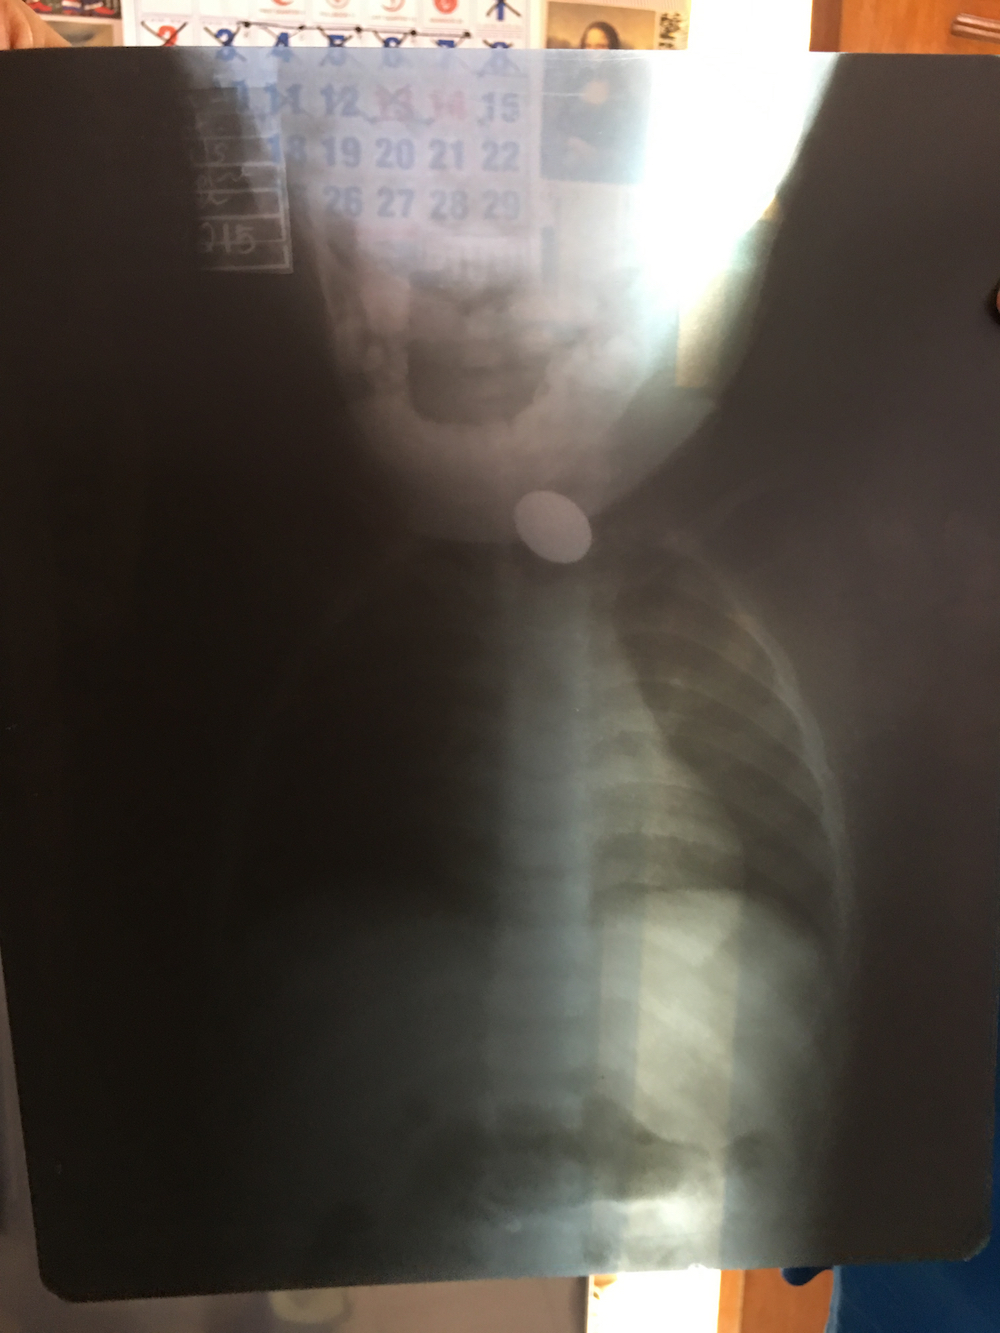

baby jyn swallows a coin

emergency OP

PS: Stopping by the house after the operation (below) baby Jyn doesn’t show any signs of being rushed to the city hospital, general anaesthetic or being pried apart to remove a coin.